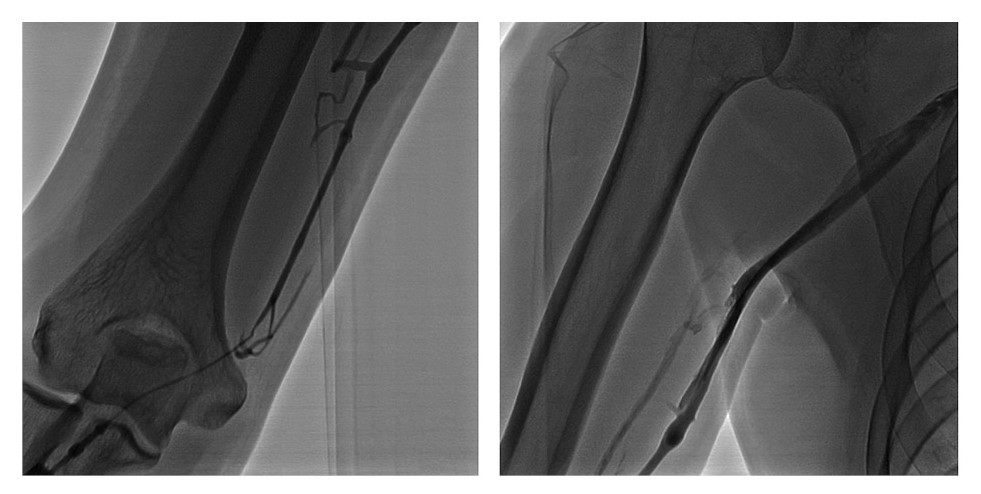

Пациенту предложено проведение повторной эмболизации вен перипростатического сплетения, но с применением внутрисосудистого неадгезивного эмболизирующего клея «КАП». С учетом данных анамнеза и КТ принято решение о ретроградном доступе к перипростатическому венозному сплетению. Под ультразвуковым контролем пунктирована локтевая вена на правой руке с последующей установкой в ней инъекционного катетера многократного использования размером 18G. Для уточнения анатомии венозной системы правой руки и выбора оптимального инструментария выполнена флебография (рис. 7), которая демонстрирует доступ к медиальной подкожной вене руки (vena basilica).

Рис. 7. Флебография v. basilica dextra через 18G катетер.

Инъекционный катетер в v. basilica по проводнику заменен на интродьюсер 5 Fr. На гидрофильном проводнике 260 см катетер perfoma hockey stick проведен в правую внутреннюю подвздошную вену, выполнена флебография в режиме цифровой субтракционной ангиографии (digital subtraction angiography – DSA), выявлен патологический дренаж контрастированной крови из системы дорсальных вен ПЧ (рис. 8).

Рис. 8. Флебограмма: а – правой общей подвздошной вены; b – части путей оттока из папапростатического сплетения.